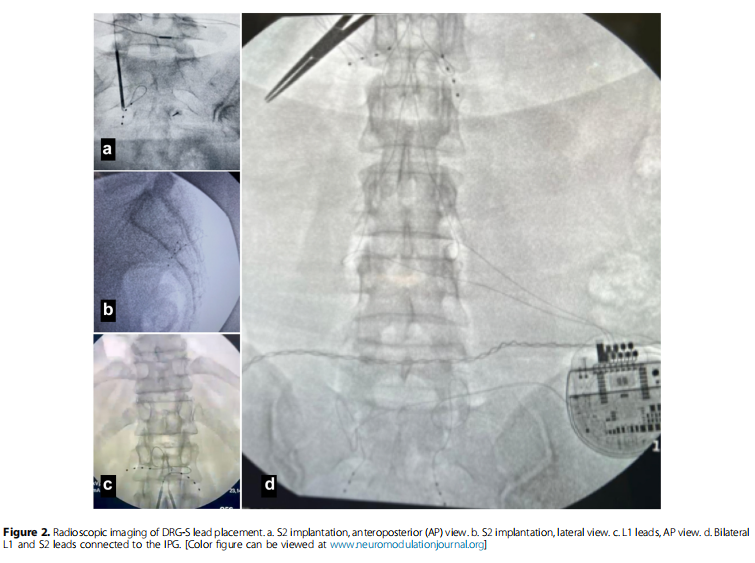

刺激触点和刺激参数

背根神经节刺激(DRG-S)手术分为两个阶段,针对双侧L1和S2背根神经节。第一阶段为测试,设置传统参数(脉冲宽度200-300μs,频率20 Hz,振幅70%-80%的痛觉阈值,通常在0.2-0.8 mA之间),并于第4天和第7天评估。若患者疼痛改善≥50%(VAS评分),则进入第二阶段,即永久植入DRG-S电极和植入式脉冲发生器于臀部。术后12个月随访,调整DRG参数以实现最佳效果。

十名患者因子宫内膜异位症引发的慢性盆腔疼痛(CPP),接受了双侧L1和S2背根神经节刺激(DRG-S)的试验性治疗。经过四至七天的试验期,九名患者符合标准,继续进行了永久植入手术;而一名患者因试验效果不佳,未能达到研究纳入标准。所有参与研究的患者,在手术前(基线)和手术后12个月,均接受了评估,评估内容包括视觉模拟评分(VAS)、麻醉药物使用情况以及SF-12生活质量调查问卷。在经过12个月的DRG刺激治疗后,9名患者的疼痛评分,如下图所示均有所下降,有效率(VAS评分降低≥50%的比例)为88.9%,表明DRG刺激在治疗此类疼痛方面具有一定的疗效。